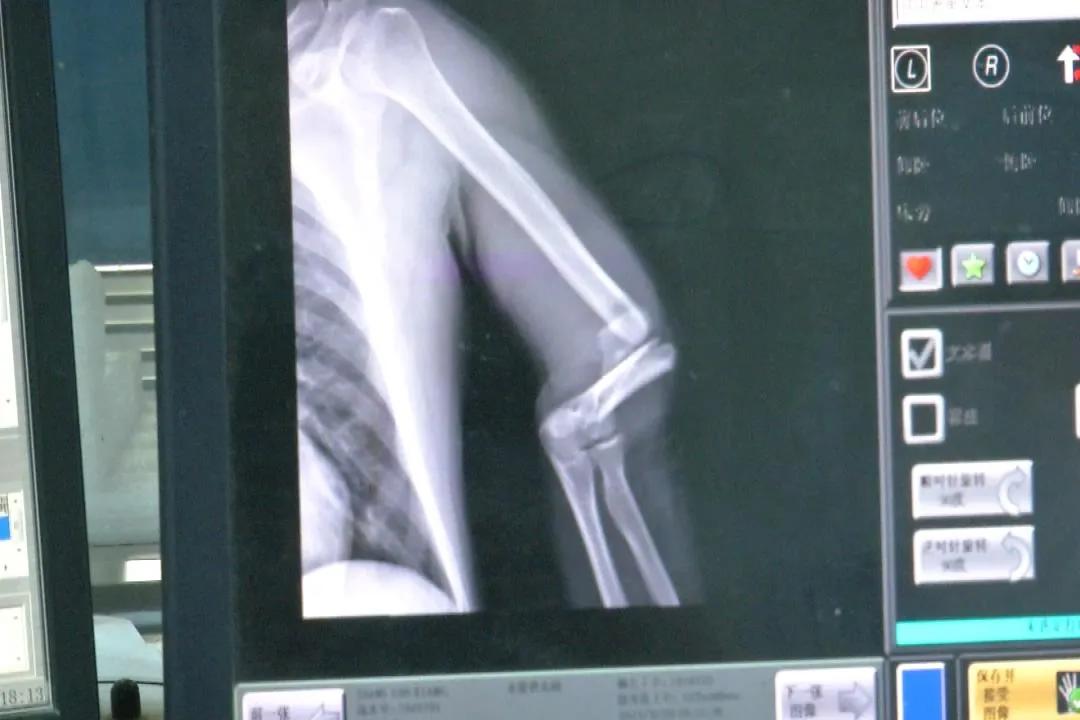

经过X光和CT检查,杨民的病情逐渐明晰。他受伤的部位远比想象中的多,伤情也很严重,多学科医生对他进行了会诊。

云南大学附属医院 急诊外科主治医师 廖鹏:“头面部有多发骨折,并且有脑挫伤,胸部有多根肋骨骨折,左侧的肱骨下端和左侧大腿都有骨折,相对来说如果骨折部位比较多,容易发生创伤性失血性休克,另外脑挫伤和胸部受伤的情况容易危及生命,等头和胸部情况稳定以后,我们才能对其它地方骨折进行下一步治疗。”